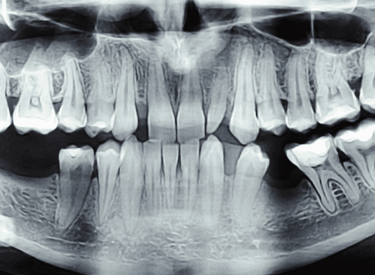

تحليل الأسنان

تحليل الأسنان للتعرف على الأشخاص (Forensic Odontology) هو مجال في الطب الشرعي يستخدم الأسنان لتحديد هوية الأفراد. تعتمد هذه العملية على أن الأسنان فريدة لكل شخص ومقاومة للغاية للتحلل والتلف، مما يجعلها مصدرًا موثوقًا للمعلومات حتى بعد الكوارث. تتم مقارنة السجلات السنية المتاحة للتعرف على الرفات المجهولة أو ضحايا الحوادث.